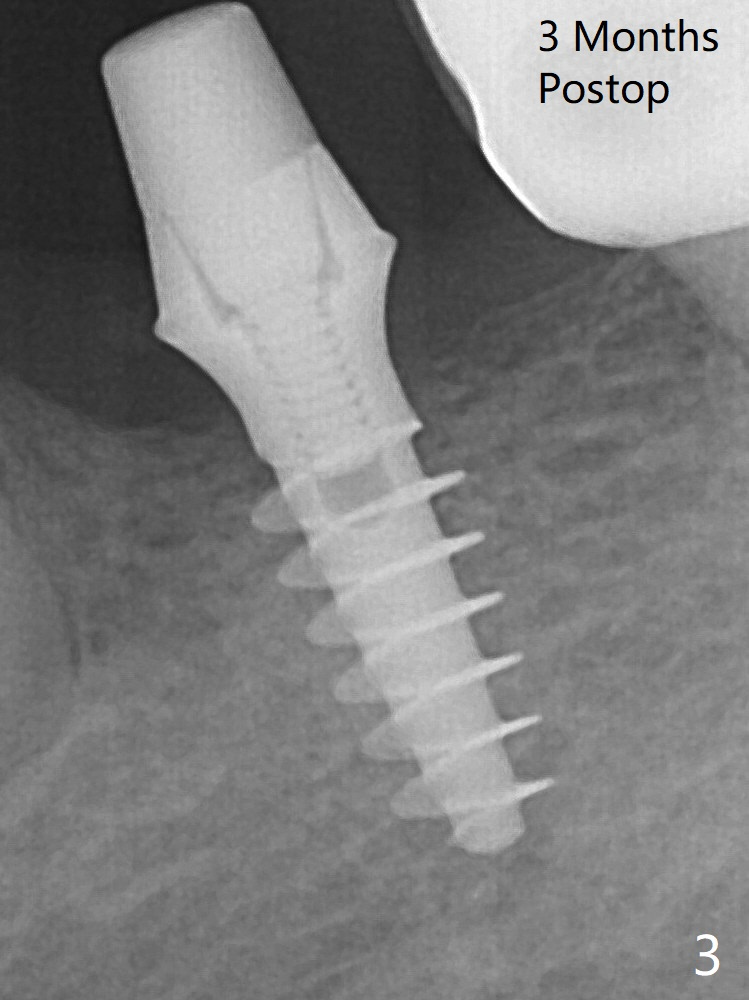

After finishing osteotomy at #19 according to IS drill sequence for 4x10 mm implant except cortical tap, a 4x9(2) mm Magicore is placed with ~ 50 Ncm (Fig.1). Thin threads are less traumatic with less bone loss. The implant with 4.5x3 mm solid abutment is stable for impression nearly 3 months postop (Fig.3). Appreciate the distinct thread pattern of Magicore 3 months 1 week postop, immediately post cementation (Fig.4).